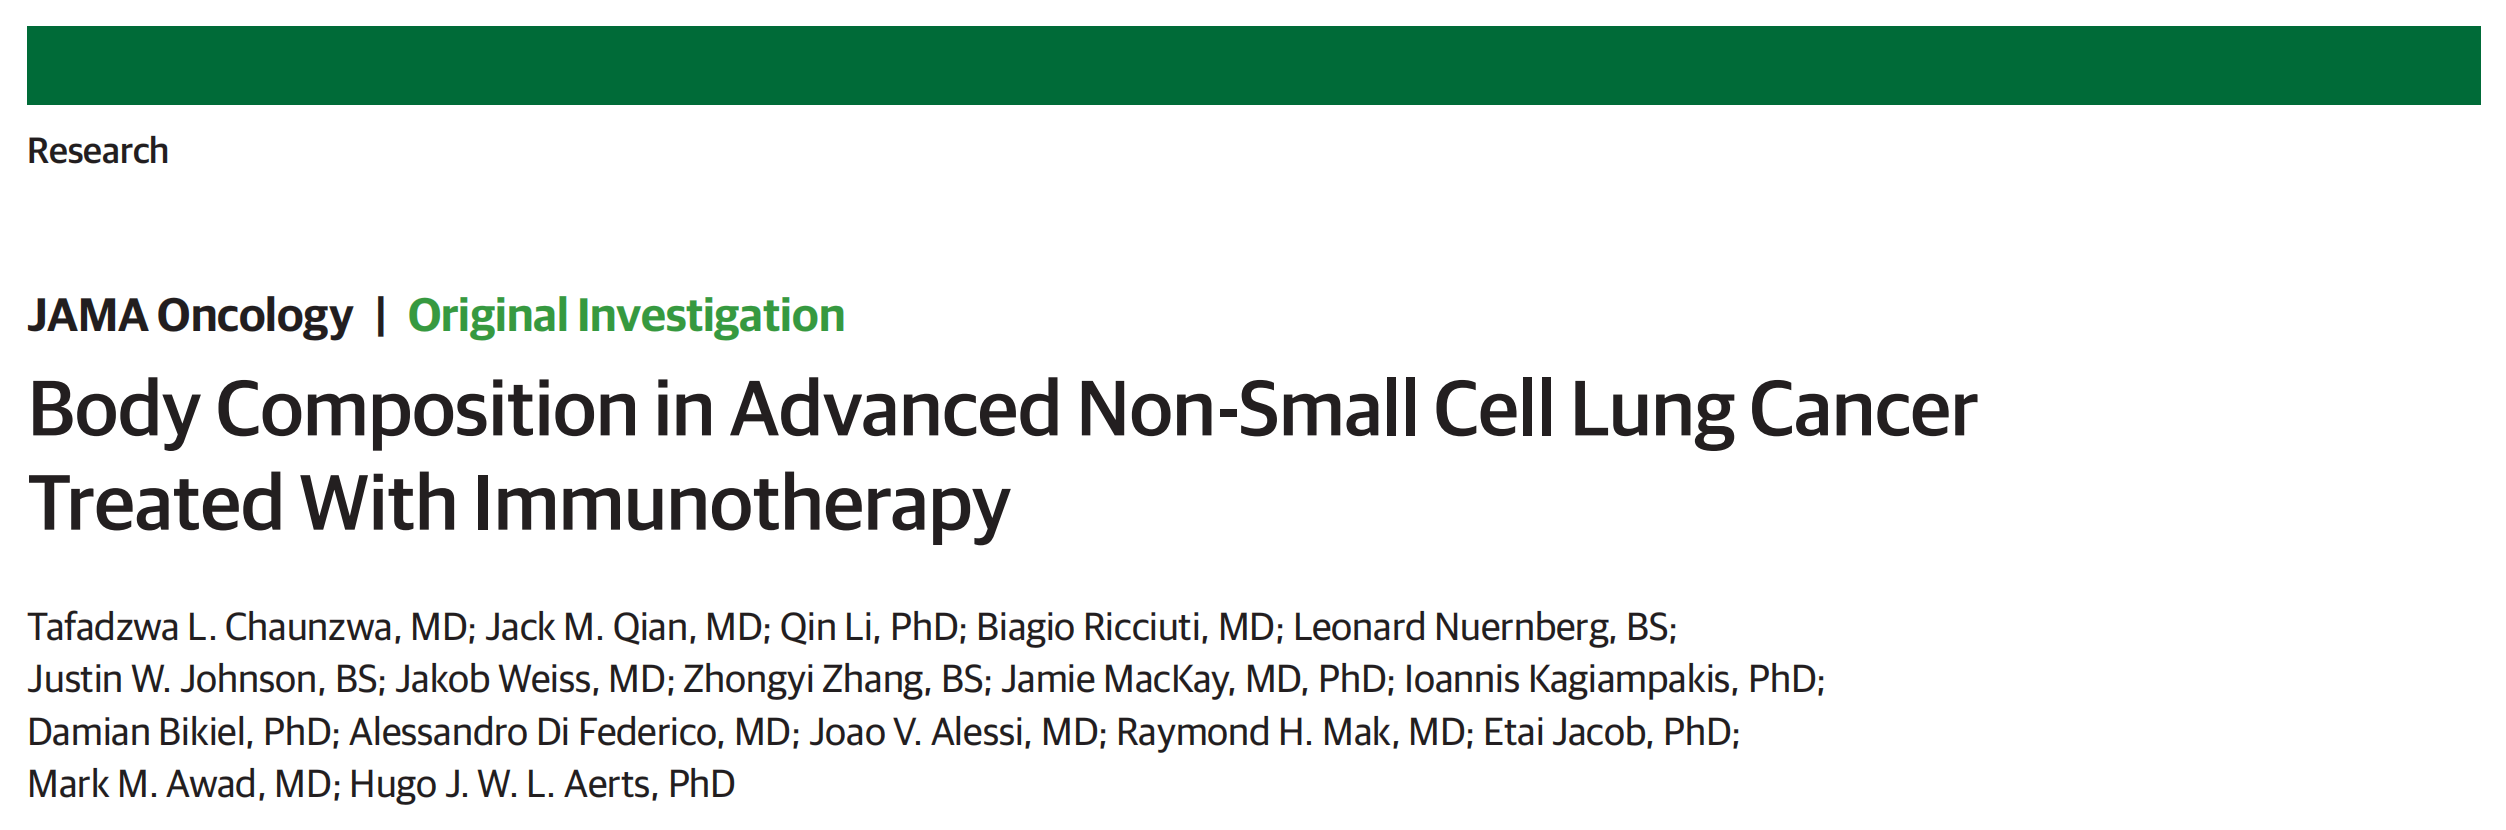

通过人工智能(AI)诊断出隐藏性转移性肺癌的三个关键图像:

(A) 后前位胸部X光片显示无异常:这张图显示了患者胸部的X光片,从后向前观察,没有发现任何异常。这表明在初步检查时,放射科医生未能发现患者的肺部异常。

(B) 人工智能生成的复查胸部X光片指出左下肺野的病变(箭头):这张图是AI系统分析后的X光片,它指出了左下肺野中的一个病变区域。AI系统通过算法识别出了人类视觉可能遗漏的异常,用箭头标记出了病变的位置。

© 胸部CT扫描显示心脏和降主动脉背侧的小结节(箭头):这张图是更详细的胸部计算机断层扫描(CT)图像,它显示了心脏和降主动脉背侧的一个微小结节。这个结节在X光片上可能因为位置的原因而被遮挡,不易被发现,但在CT图像中可以清楚地看到。

分析这三个图像,我们可以看到:

- AI的辅助作用:AI系统能够识别出人类可能忽视的病变,这对于提高诊断的准确性至关重要。

- 病变的位置和隐蔽性:病变位于心脏和降主动脉的背侧,这个位置在常规X光片上可能不易被观察到,说明了某些病变的隐蔽性和复杂性。

- 诊断技术的差异:CT扫描提供了比普通X光更详细的图像,有助于更准确地识别和定位病变。

这些图像和分析结果强调了AI在医疗诊断中的重要性,尤其是在提高早期发现和治疗癌症方面的潜力。同时,它们也展示了不同成像技术在诊断过程中的互补性。